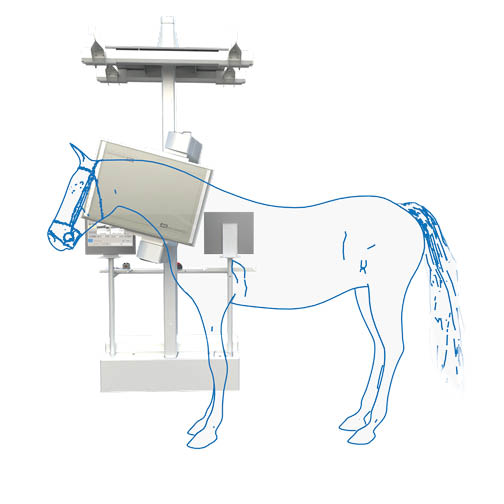

Scintigraphy on a Standing Horse

An ingenious combination of mechanics, electronics, and software makes scintigraphy on a standing horse easily achievable. Experience gained from human medicine, including detector specifications, measurement methods, and processing, as well as feedback from our many customers, has enabled us to achieve the goal of easy and fast diagnosis.

It is compact, robust, and mechanically superior to pendulum suspension systems. The detector support column is mounted approximately one centimeter above the floor, allowing quick and easy movements along any axis of the gantry support. Thus, the gantry operates at a low noise level.